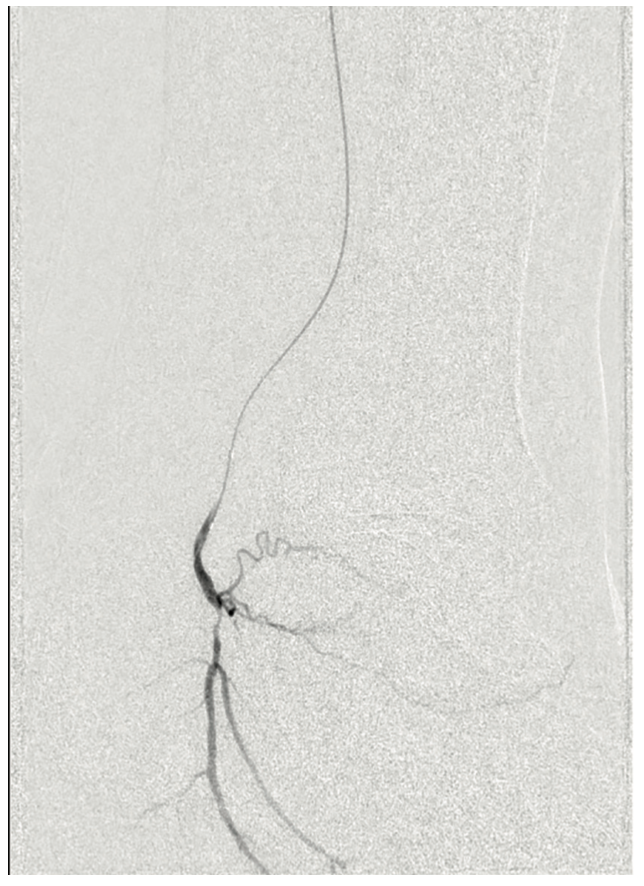

The patient was heparinized. A long 6 French Destination sheath (Terumo Interventional Systems) was used to cannulate the femoral-popliteal artery with an .035-inch system. We then selectively cannulated the posterior tibial artery with an .014-inch Grand Slam wire (Asahi Intecc). Using an .014-inch catheter and wire, we were able to pass through the distal posterior tibial artery stenosis into the pedal vessels. We started with a 2.0 mm plain balloon (POBA), resulting in recoil (Figures 3-4). We then used a 2.5 mm diameter Serranator PTA Serration Angioplasty Balloon (Cagent Vascular) (Figure 5) and achieved significant lumen gain without recoil. The peroneal artery lesion was also treated with angioplasty. The posterior tibial artery was considered to be the most important for wound healing, as the peroneal artery mostly terminated at the ankle level and the posterior tibial artery had strong dominant flow into the left foot. In addition, the anterior tibial and dorsalis pedis pathway was chronically occluded and essentially clinically nonexistent.

The final imaging of the posterior tibial artery demonstrated a surprisingly positive angiographic result with brisk blood flow and was clinically satisfactory (Figure 6). We were encouraged with this outcome, and optimistic for eventual wound healing.